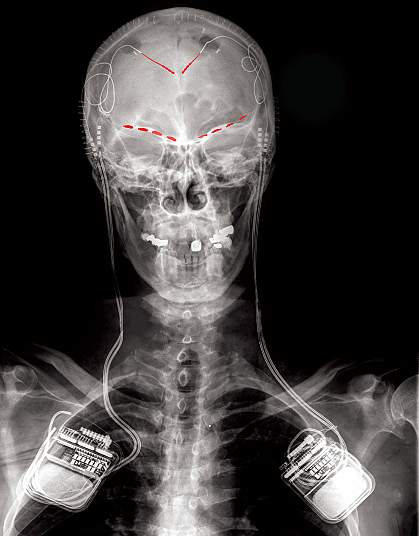

The participants had electrodes surgically implanted in two brain regions— the anterior cingulate cortex (ACC) and the orbitofrontal cortex (OFC)—to study an approach called deep brain stimulation. These regions have been implicated in different aspects of the pain response. The electrodes recorded activity in these brain regions over several months. During this time, the participants rated the intensity of their pain multiple times a day. Results from the study appeared in Nature Neuroscience on May 22, 2023.